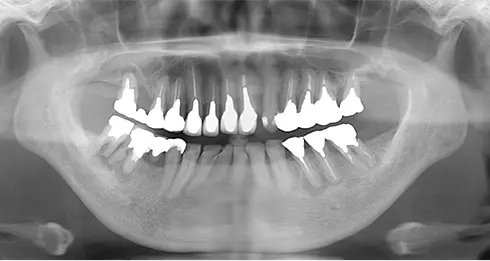

| 年齢/性別 | 50代女性 |

| 主訴 | 左下奥歯に痛みがある、全体的に治したい |

| 治療内容 | 全体的に歯周病やむし歯、根の治療を行い、仮歯を使用して咬合治療を実施。右下2本、左下1本の計3本を抜歯し、その後、右下に2本、左下に2本の計4本のインプラントを埋入しました。 |

| 治療期間 | 8か月 |

| 費用 | 2,106,500円税込 |

| リスク・副作用 | 炎症反応によって術後に腫れが生じることがあります。その程度は、手術の範囲や方法によって異なりますが、多くの場合、時間の経過とともに徐々に治まります。 ごく稀に、下顎奥歯の外科手術後に、唇や顎に痺れを感じることがあります。 |